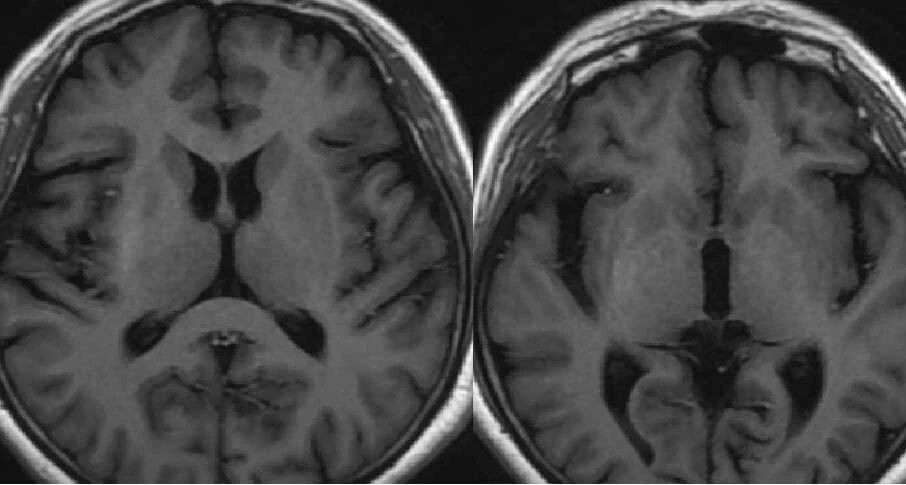

3 天后行 MRI 检查,图像如下:

T1WI 示病灶呈高信号,T2WI 呈低信号,DWI 信号不高,病灶边界清晰,无占位效应及周围水肿,内囊未累及。

女,58 岁,右侧肢体持续性不自主扭动,既往糖尿病史 20 年,测血糖为 12.17 mmol/L,HbA1c 为 14.5%。CT 示左侧豆状核高密度,边界清晰。T1WI 示病灶呈高信号,T2WI 呈低信号,边界清晰,无占位效应及周围水肿,未累及内囊,增强后未见强化。

女,58 岁,非酮症高血糖性偏侧舞蹈病。CT 示右侧尾状核头及豆状核弥漫性高密度。MRI T1WI 示病灶呈高信号,T2WI 呈低信号,边界清晰。病理切片示右侧基底节出血。